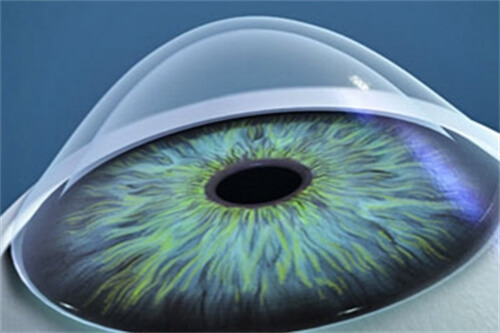

在可靠技术方面,雷医生擅长玻璃体视网膜手术,对复杂性视网膜脱离、糖尿病视网膜病变、黄斑裂孔、黄斑前膜等疾病有独到的治疗经验。

她采用小创口玻璃体切割技术,结合较可靠的眼科检查设备,为患者制定个性化治疗方案。

小创口玻璃体切割术:使用25G/27G超小创口系统,创伤小、修复快